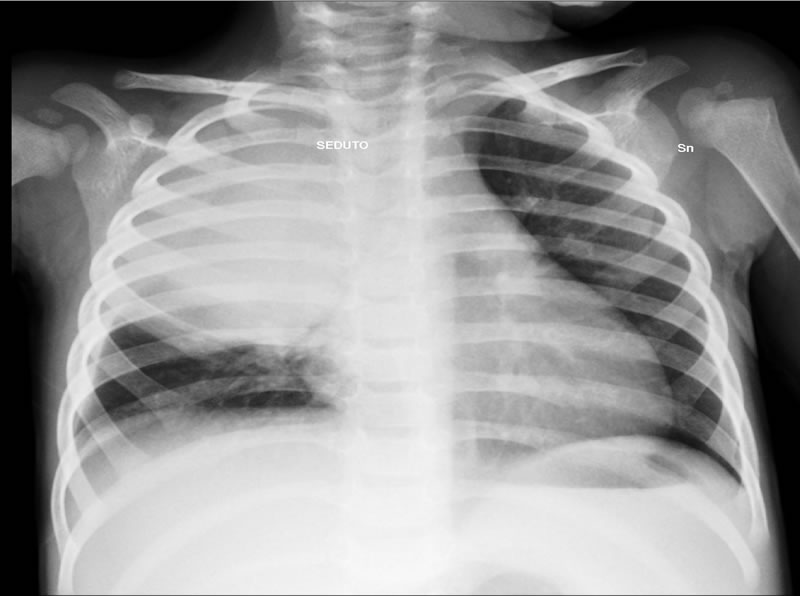

Alla radiografia del torace presenza di focolaio broncopneumonico dx (Figura 1)

Figura 1

Focolaio BPN dx che interessa il lobo superiore e medio, con piccola falda di versamento Figura 2